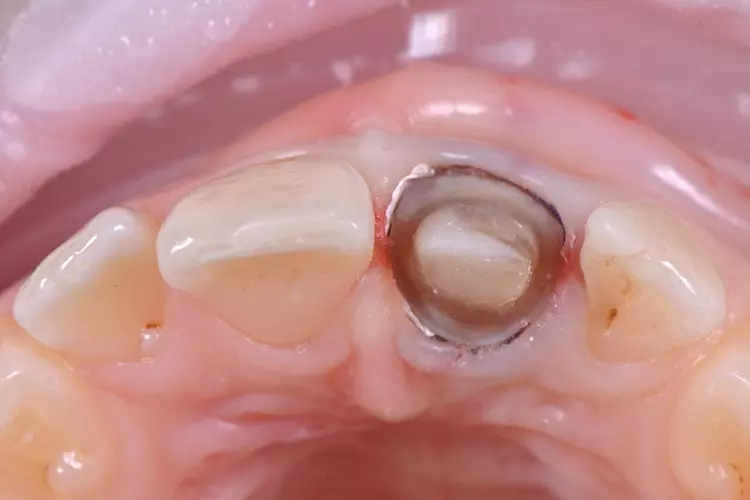

Im Rahmen des Erstgespräches berichtete die junge Patientin von einem Sturzereignis, bei dem der Schneidezahn frakturierte. Ihr damaliger Zahnarzt führte eine Wurzelkanalbehandlung durch und versorgte den Zahn mit einer Krone aus Lithiumdisilikat. Das anfänglich sehr ansprechende ästhetische Behandlungsergebnis hätte sich jedoch nach der Eingliederung mit der Zeit verändert und die Patientin stellte eine zunehmende Verfärbung der Frontzahnkrone fest (Abb. 2 und 3).

Dies kann aus einer nachträglich eingetretenen Verfärbung des devitalen Zahnes resultieren. Durch die sehr hohe Transluzenz der Glasphase einer Lithiumdisilikat-Restauration kann die dunkle Stumpffarbe durchschlagen und zu einem ästhetisch störenden „Grauschleier“ führen. In einem intensiven Beratungs- und Aufklärungsgespräch wurden der Patientin die Schwierigkeiten und Herausforderungen einer Einzelzahnkrone in der ästhetischen Zone bei einer hohen Lachlinie mit Exposition der Gingiva dargestellt.

Manche Details wie die Verfärbung der Gingiva wären nicht korrigierbar und verringerten die Vorhersagbarkeit eines optimalen ästhetischen Resultates. Die Neuversorgung dient der Verbesserung der ästhetischen Situation, eine perfekte Kopie des Zahnes 11 wird nicht zu erzielen sein, da die verfärbte Wurzel bestehen bleibe.